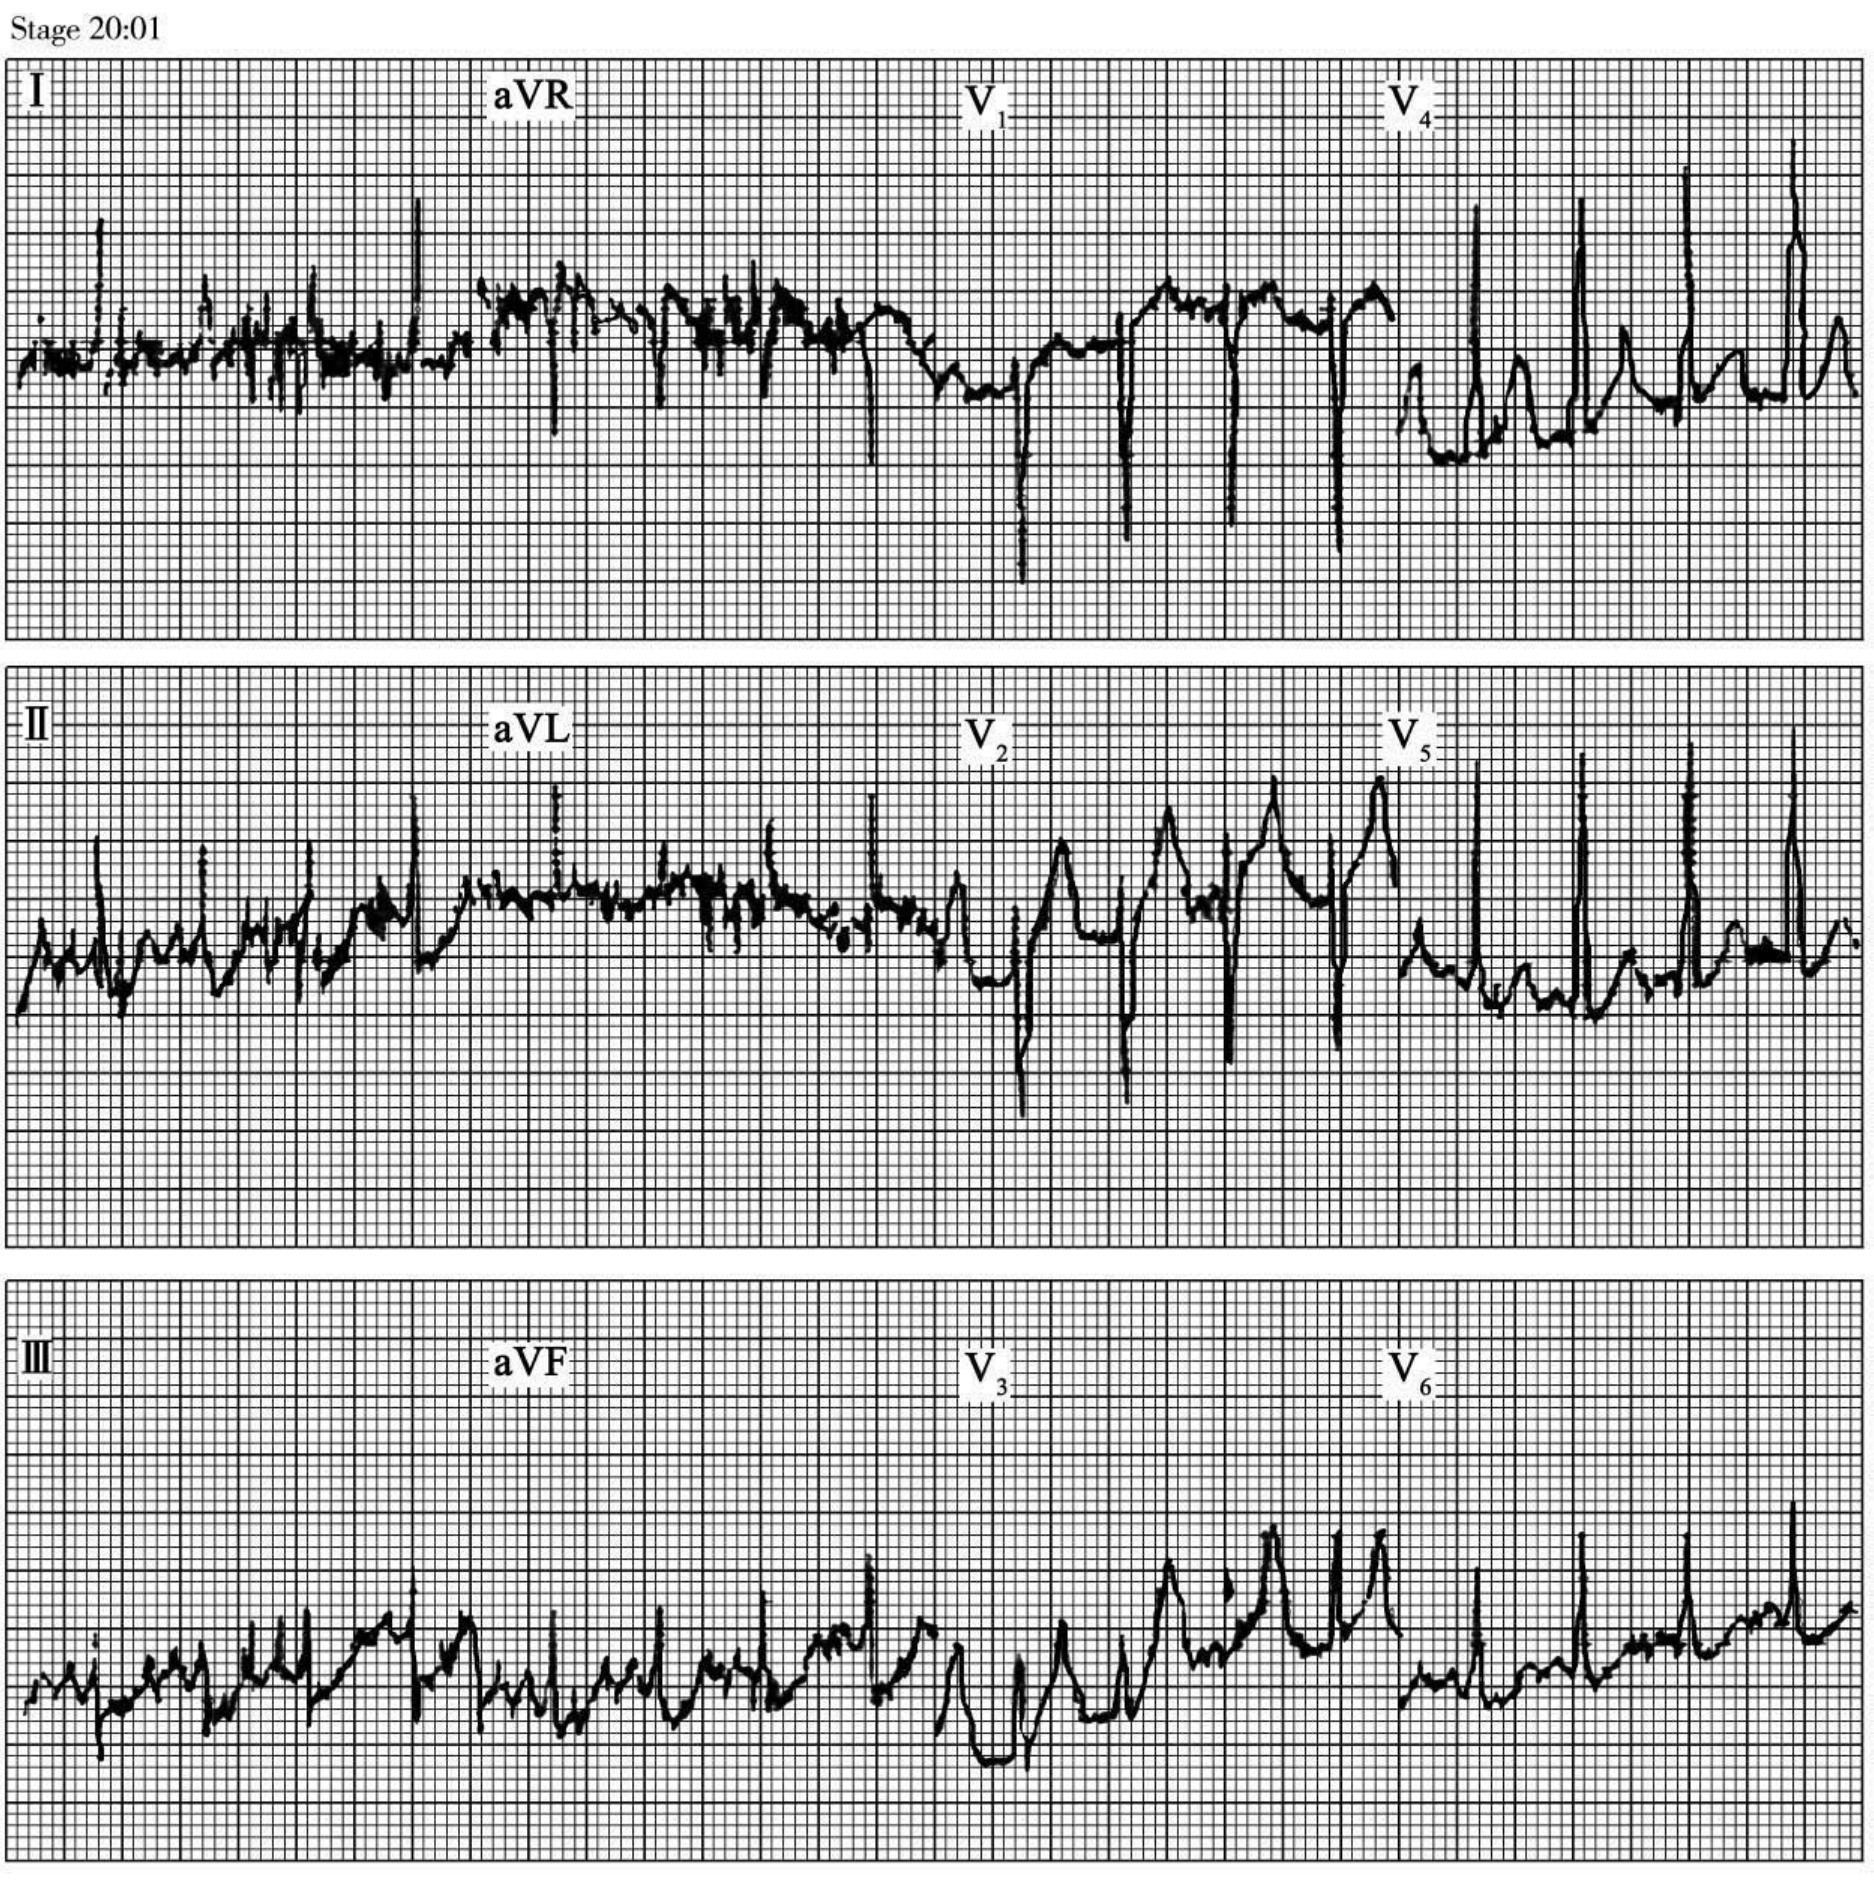

七、运动试验的安全性和危险性

运动试验已经被证实是一项安全的无创性检查,目前较公认的死亡率约为0.1‰,并发症的发生率为0.24‰。运动试验的危险性受运动方法、病历选择、实验室条件等因素的影响。常见的心脏并发症:有心律失常(图63-7)、心脏性猝死、心绞痛和心肌梗死、心力衰竭、高血压和低血压。

图63-7 运动试验中发生的心律失常

(1)运动前心电图

(2)

(3)

图63-7 (续)运动试验中发生的心律失常

(2)发生室性心动过速前的心电图;(3)运动中突发室性心动过速,立即终止运动所记录的心电图

(3)图63-7 (续)运动试验中发生的心律失常

(3)运动中突发室性心动过速,立即终止运动所记录的心电图

(4)图63-7 (续)运动试验中发生的心律失常

(4)在恢复期再次出现的室性心动过速

(4)

(5)

(5)在室性心动过速后出现ST段抬高

(6)

(7)

(6)抬高的ST段逐渐恢复过程;(7)在ST段抬高恢复后出现的ST段压低

(8)图63-7 (续)运动试验中发生的心律失常(7)在ST段抬高恢复后出现的ST段压低;(8)sT段恢复

(8)图63-7 (续)运动试验中发生的心律失常

(8)sT段恢复